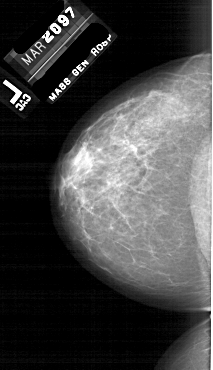

A_1764_1.LEFT_CC

LEFT_CC LINES 5911 PIXELS_PER_LINE 3406 BITS_PER_PIXEL 12 RESOLUTION 43.5 NON_OVERLAY